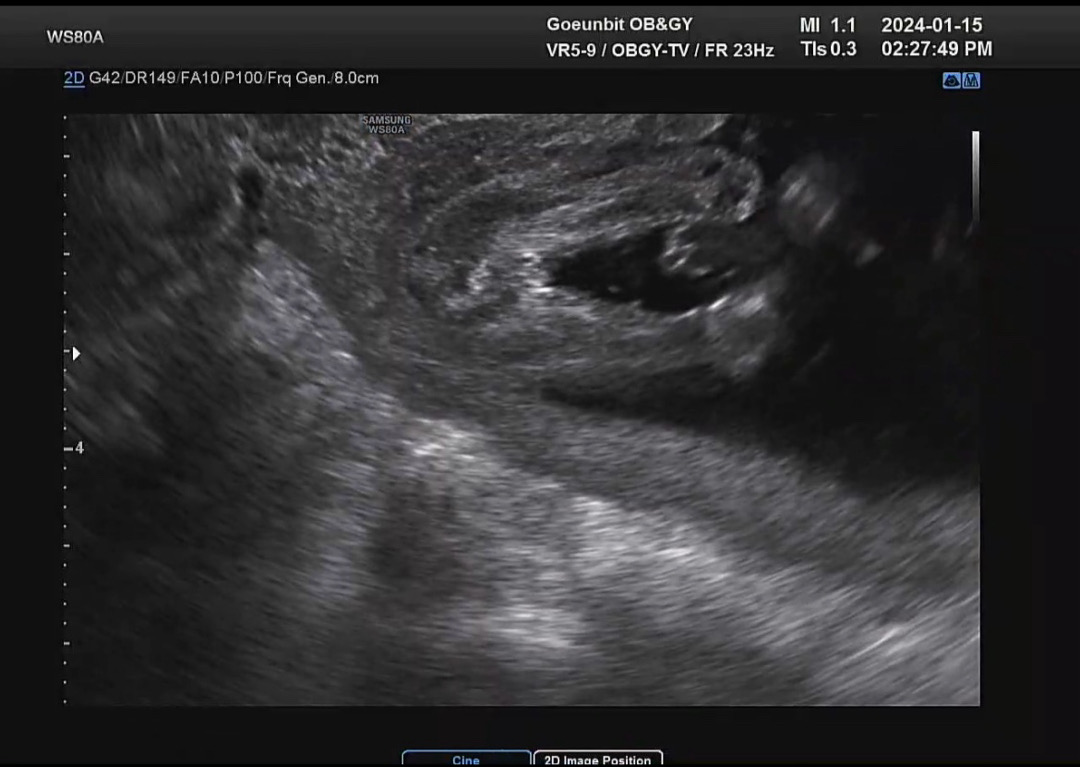

오늘 다리사이 사진 찍었는데요! 담당쌤이 저번엔 남자에 한표 던지셨고, 오늘은 담당쌤 쉬셔서 다른 쌤한테 진료봤는데 이분은 여자일 것 같다고 하셔서요~ 뭐가 맞는걸까요!!!

딸램인것같은데용!! 헉 12 주때 초음파사진궁금해요 .. 저도 아들이라고하셨는데 지금반전 기다리고있는중이에요ㅠㅠㅠ

여기 댓글엔 사진이 안올라가네요ㅠㅠ 12주땐 뭘 보시고 아들이라고 그러신거지...? 할정도로 저는 안보였어요🥺 아기가 너무 움직여서도 못봤구요!